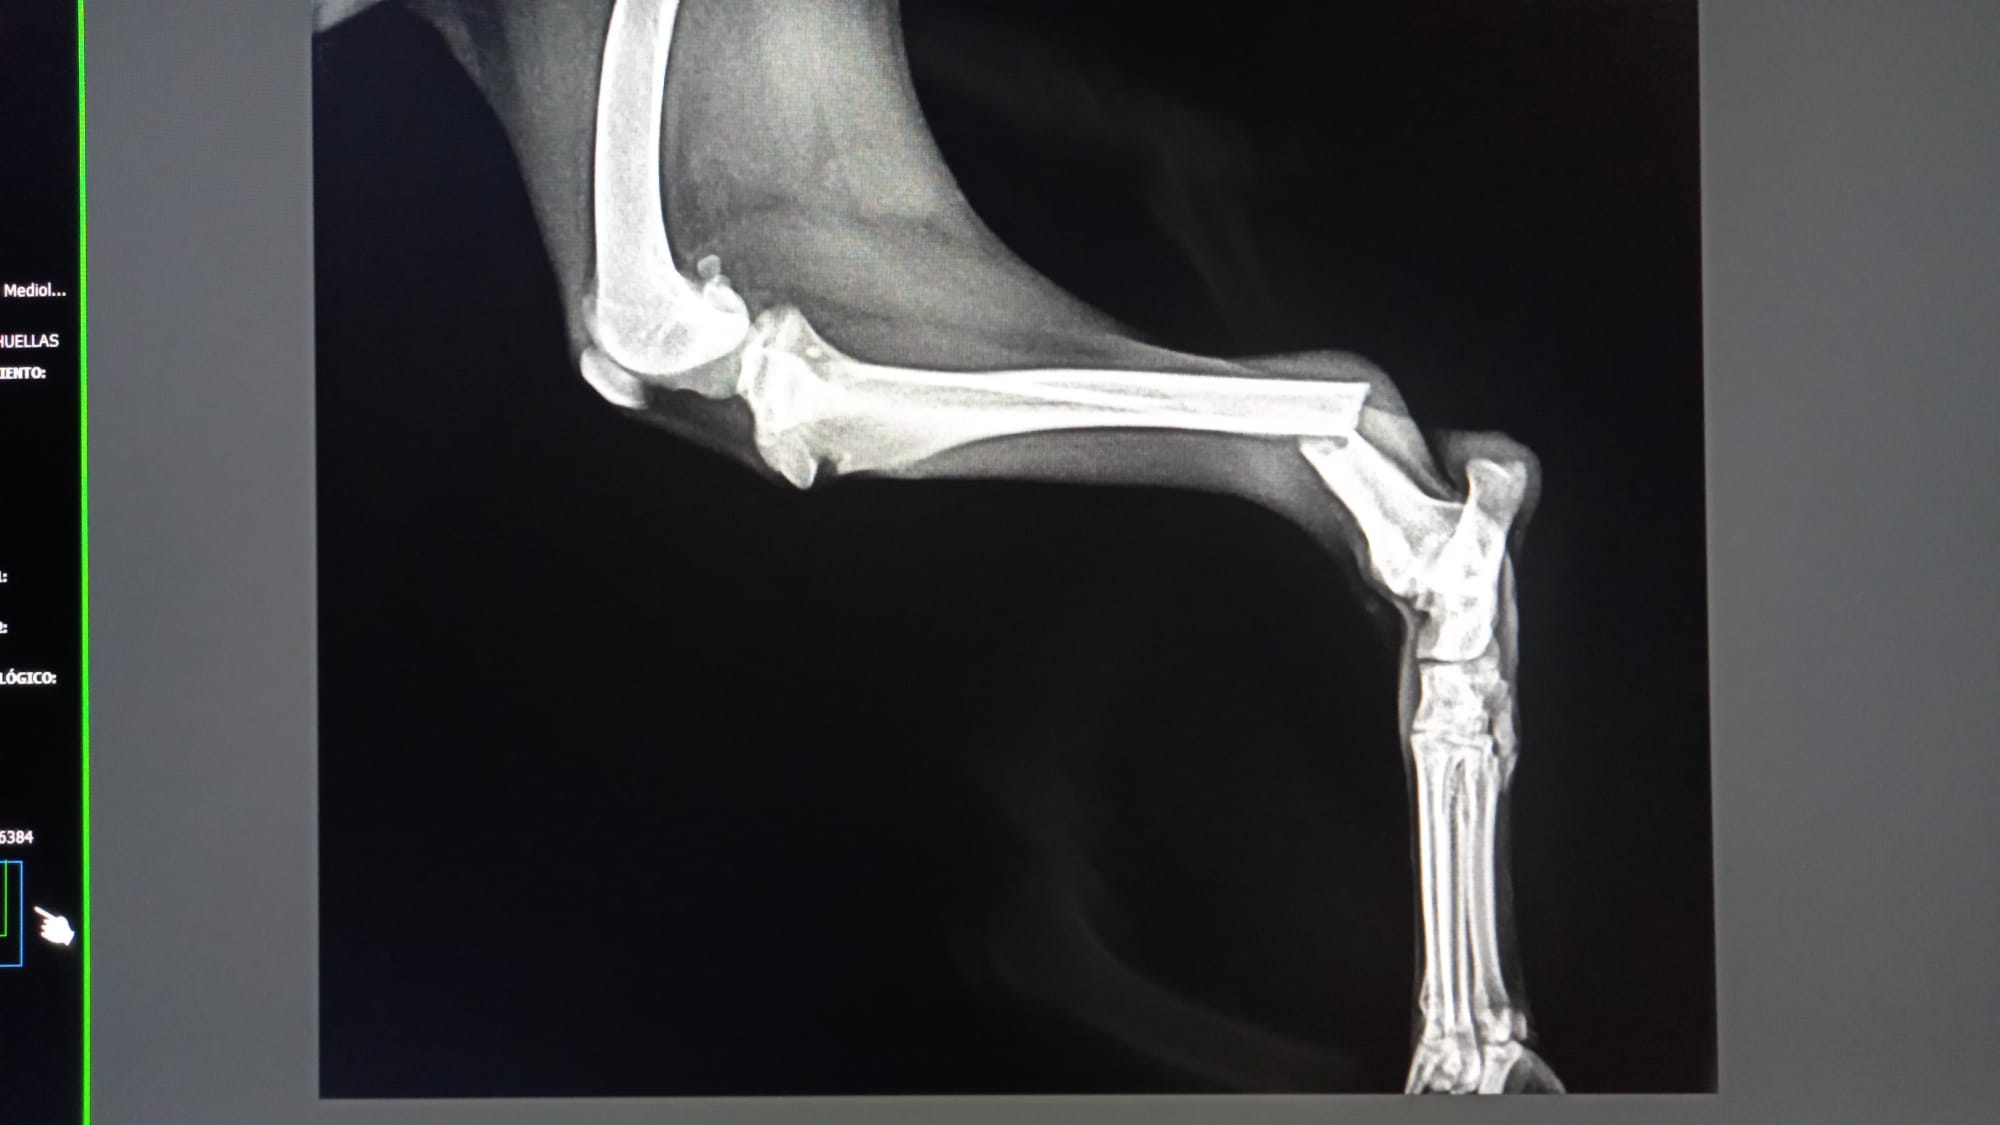

A pesar de estar en una situación crítica como siempre , hace mucho que no os pedimos ayuda, pero os necesitamos urgentemente. Nos ha llegado, además de las entradas constantes al albergue, dos casos muy complicados , una perrita (JESSY) con casi todos los dientes mal, hernias, tumores……y una bretoncita (ADARA) con la pata rota, cada una de las facturas asciende a 1.000 euros, y no sabemos cómo hacer frente, a los 2.000 euros de las factura,  ya sabéis que la subvención municipal no llega ni a la cuarta parte del gasto anual de esta protectora y que además de este año 2.023 no hemos recibido ni un solo euro a día 7 de julio .